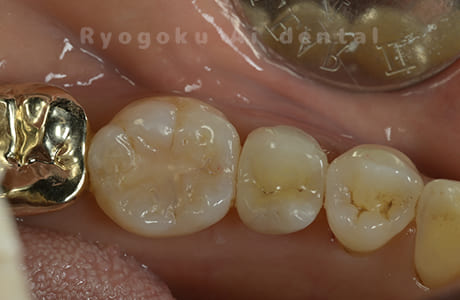

Case11

- 治療内容

- セラミッククラウン、セラミックインレー

-

- 治療費用

- 123,000円×2(セラミッククラン)、77,000円(セラミックインレー)

銀歯が取れて、ご来院された患者様です。奥歯2本をセラミッククラウン、手前の小臼歯をセラミックインレーで治療を行いました。